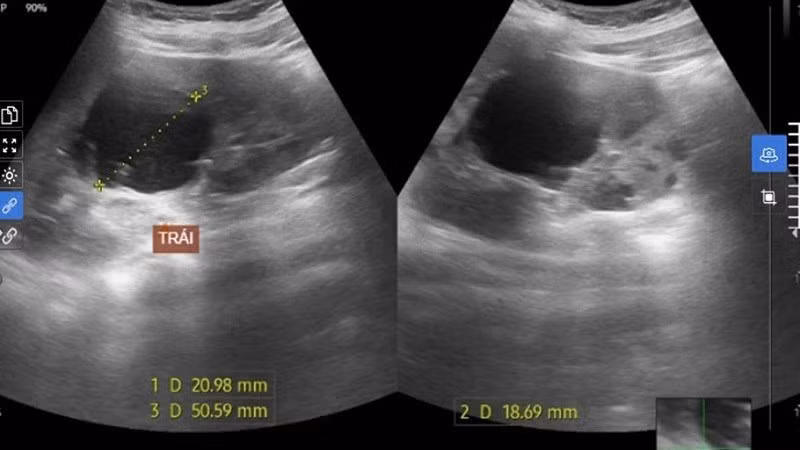

Hình ảnh siêu âm nang thận của bệnh nhân.

Những kết quả khám đáng lưu ý gồm hình ảnh siêu âm bụng phát hiện thận đa nang hai bên (thận trái hơn 7 nang, thận phải hơn 10 nang), kích thước thận to. Hiện, chưa có suy giảm chức năng thận.